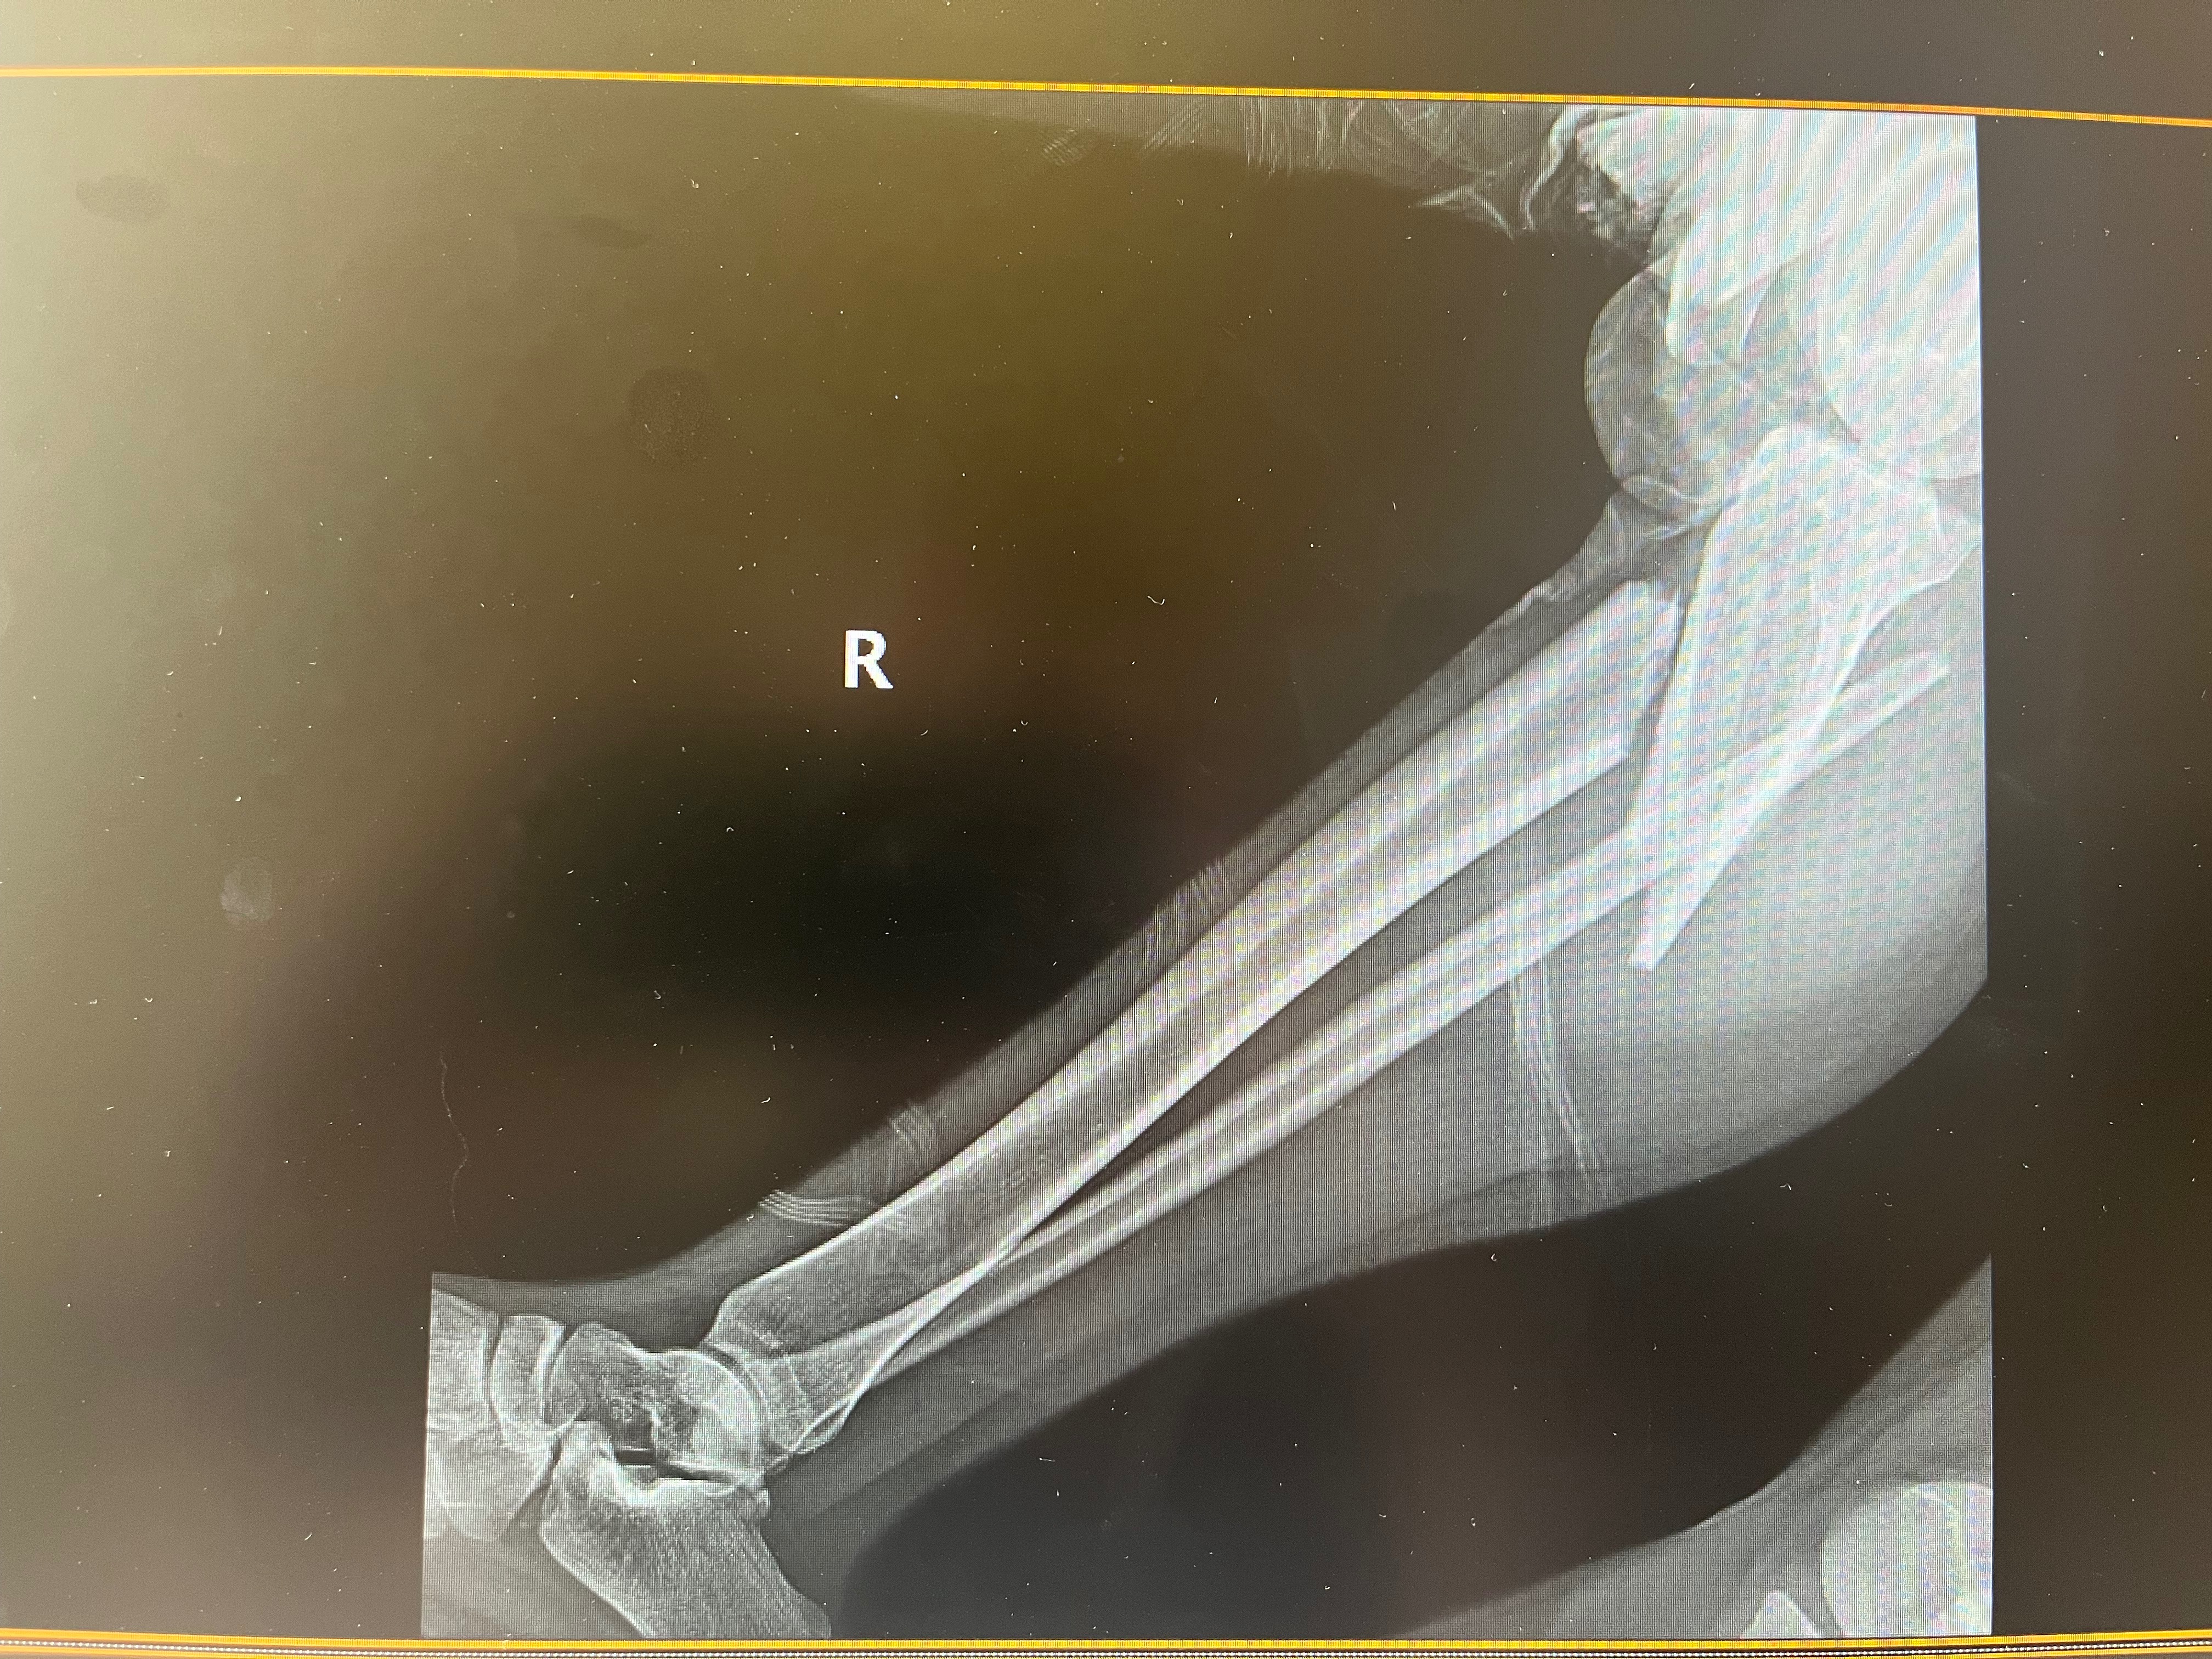

This is Kimmora. She was involved in a life-changing accident…. Please help her get back on 2 feet. She broke her femur and multiple other bones. She’s 19 and could really use all the help and support from the community. She is currently in the hospital recovering from the accident.